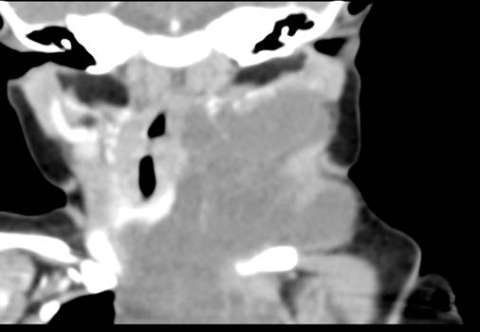

The lesions are most commonly evaluated with contrast enhanced MRI. Occasionally US and CT are used.